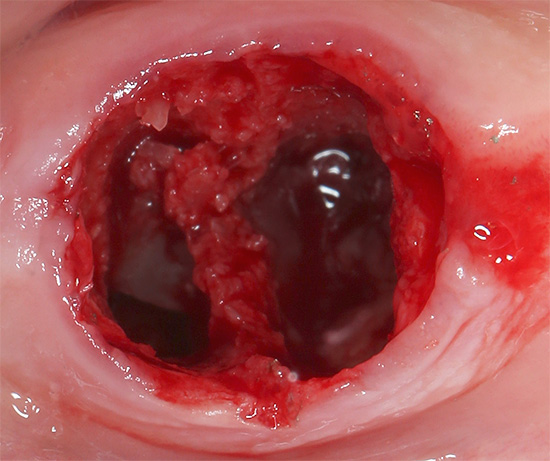

A foto abaixo mostra como o buraco fica logo após a remoção do dente do siso, anteriormente escondido sob a gengiva: